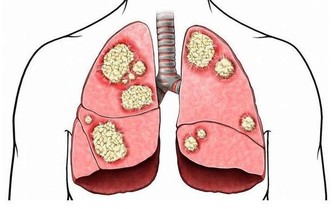

既然低體溫容易罹患癌症,那麼高溫是不是可以殺滅癌細胞呢?答案是這絕對是可以的!這不是開玩笑,熱療已經成為對付腫瘤的一種新方法,國外醫學家甚至將它稱作「醫療春天的到來」。 從世界範圍來看,被稱為「醫學之父」的古希臘名醫Hippocrates也曾用加熱法來治療腫瘤。一百多年前,德國醫生Coley發表了有關「發熱療法」的研究,往患者體內注射「Coley毒素」誘發患者發熱,他用這種方法治療了38例晚期癌症。癌症細胞比正常的人體細胞更為「怕熱」,所以,在同樣的加熱溫度下,癌細胞熱得停止生長,正常的組織細胞卻依然可以「悠哉游哉」。這樣一來,既能殺滅腫瘤組織,又可以最大限度避免「誤傷」正常組織。 有人也曾經試過把自己架在火上烤,希望藉此能殺滅體內的癌細胞,這就有點「病急亂投醫」了,因為人體的導熱性比較差,烤火或者蒸桑拿無法將熱量傳遞到腫瘤組織,所以起不到殺滅癌細胞的作用。如果將身體長時間暴露在高溫之下,可能會導致身體組織脫水和灼傷,這是得不償失的一種做法。 而且熱療對實體腫瘤效果比較明顯,而對於白血病幾乎沒什麼效果,因為白血病的病源在骨髓中,我們目前的醫學是無法讓高溫進入全身骨髓的。所以與其等患了癌症再去找方法,不如學會預防癌症。 既然我們知道低溫是癌細胞最喜歡的溫度,那就設法提升自身溫度,把癌細胞滋生的溫床徹底掀翻掉!醫學研究表明,體溫每升高1℃,人體免疫力就會提高30%;相反,體溫降低,免疫力就會下降。 怎樣提高基礎體溫呢?試試下面的方法吧。 1. 每天喝五杯白開水,持之以恆。 2. 少淋浴,多泡熱水澡,使血液循環更暢通,保持?的活性。 3. 增加體力勞動,至少在家做家務少用吸塵器、洗衣機之類的,親自動手吧。 4. 夏天少開冷氣。 5. 不要過分減少鹽分的攝入。 6. 不要過度飲食,少吃冰冷的食物。 其中最重要的就是第一點,現在很多人都用純凈水來代替白開水,這並不是一種健康的習慣。如今日本很流行白湯排毒法,也就是要把水煮沸,然後喝溫熱的白開水排毒!這種療法源自於印度的阿育吠陀(Aayurveda) ,只要身體熱起來就能達到和用芝麻油按摩讓身體熱起來同樣的效果!,由於簡單又不必花錢,因此日本藝人千葉麗子推薦之後, 一群明星也效仿,成功造成一股風潮 煮開並沸騰3分鐘的開水,可以使水中的氯氣及壹些有害物質被蒸發掉,同時又能保持水中對人體必須的營養物質。堅持每天五杯白開水,不僅能提高基礎體溫,還有很多意想不到的效果喔! 1. 緩解便秘,多喝白開水可以促進胃腸蠕動,軟化大便。 2. 利尿,白開水有利尿的功效,可以使輸尿管、膀胱流暢,防止結石發生和細菌感染。 3. 幫助身體排毒,喝熱水時體溫上升,會使得毒素隨汗液一起排出體外。 4. 減少痛經,白開水的熱量對腹部肌肉有著鎮靜和舒緩的效果,能有效減少痛經。 5. 減肥,喝白開水能促進新陳代謝,有助於分解脂肪組織。 6. 緩解咳嗽和喉嚨痛,白開水是天然的感冒良藥,它的化痰效果使你的喉嚨不會有那麼重的異物感,而且喝幾口白開水,鼻子也很容易通氣。 喝白開水也不能盲目地硬灌,最好分時間段飲用,效果會倍增喔。 1. 早晨剛起床,此時正是血液缺水狀態。 2. 上午8時至10時左右,可補充工作時間流汗失去的水分。 3. 下午3時左右,正是休息的時刻。 4. 睡前,睡覺時血液的濃度會增高,如睡前適量飲水會沖淡積壓液,擴張血管,對身體有好處。 很多人往往在口渴時才想起喝水,而且往往是大口喝,這種做法也是不對的。喝水太快太急會無形中把很多空氣一起吞咽下去,容易引起打嗝或是腹脹,因此最好先將水含在口中,再緩緩喝下,尤其是腸胃虛弱的人,喝水更應該一口一口慢慢喝。 從今天開始記得要每天都喝溫熱開水,提早預防癌症!癌症是十分頑強的一種病症,千萬不要等到患病後才後悔為何沒有早預防。了解癌細胞的生存環境,知道它的弱點,將癌症扼殺在搖籃里。把這篇文章分享出去,讓大家都深入了解一下吧!